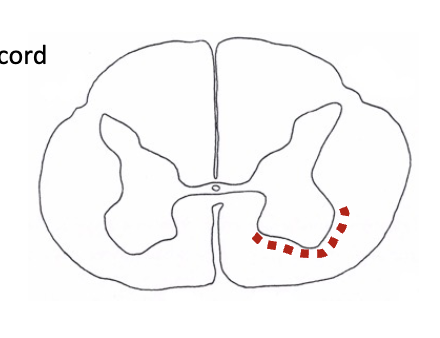

direct motor pathways

• corticospinal tracts:

• _____ corticospinal tract: all fibers have crossed here

• _____ corticospinal tract: cross in the spinal cord

lateral, ventral